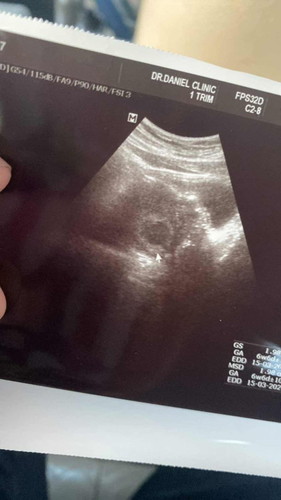

ประสบการณ์การท้องแล้วก็แท้ง เป็นอะไรที่ทรมานมากกก เสียใจเสียน้ำตาแล้วยังต้องขูดมดลูกอีก แล้วทรมานที่สุดเพราะขูดสดๆไม่ฉีดยาไม่วางยาสลบอะไรทั้งนั้น ท้องแรกแล้วไม่เคยคลอดแล้วยังต้องมาโดนขูดมดลูก ไม่กล้าท้องเลยค่ะกลัวแท้งแล้วต้องขูดมดลูกอีก ตอนขูดมันเหมือนจะตาย ณ ตอนนั้นเลยปวดท้องสุดเดินร้องไห้กลางรพ.เลย ทำไมเขาไม่วางยาสลายให้เราก่อน🥹🥹 #ขูดมดลูก #แท้ง #ขูดมดลูกสด